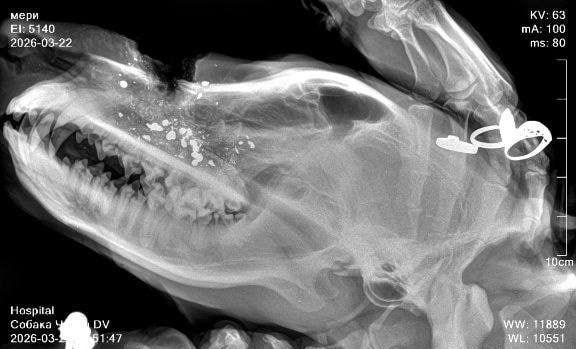

В результате нападения одна собака погибла, пострадали еще как минимум три. Двое пострадавших псов убежали, а третьего экстренно доставили в ветеринарную клинику, сообщают местные. Полиция проводит проверку.